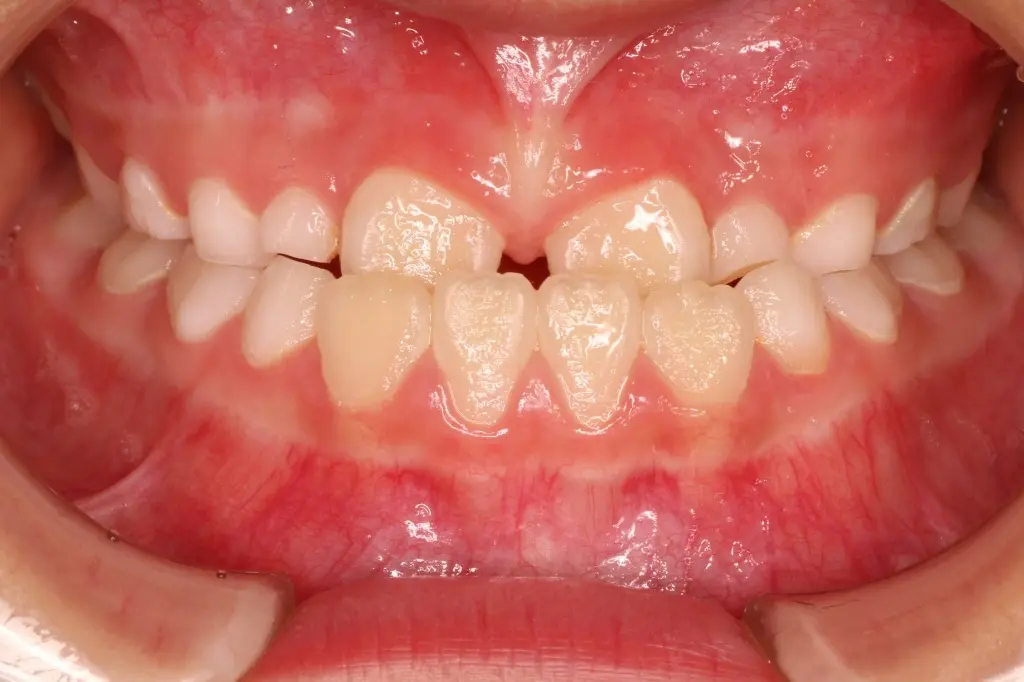

治療開始 8ヶ月後 治療8ヶ月後の状態

【反対咬合の改善】

トレーニングと装置の使用により、上の前歯が前に出て反対咬合が改善しました。この後も治療・経過観察を継続していきます。